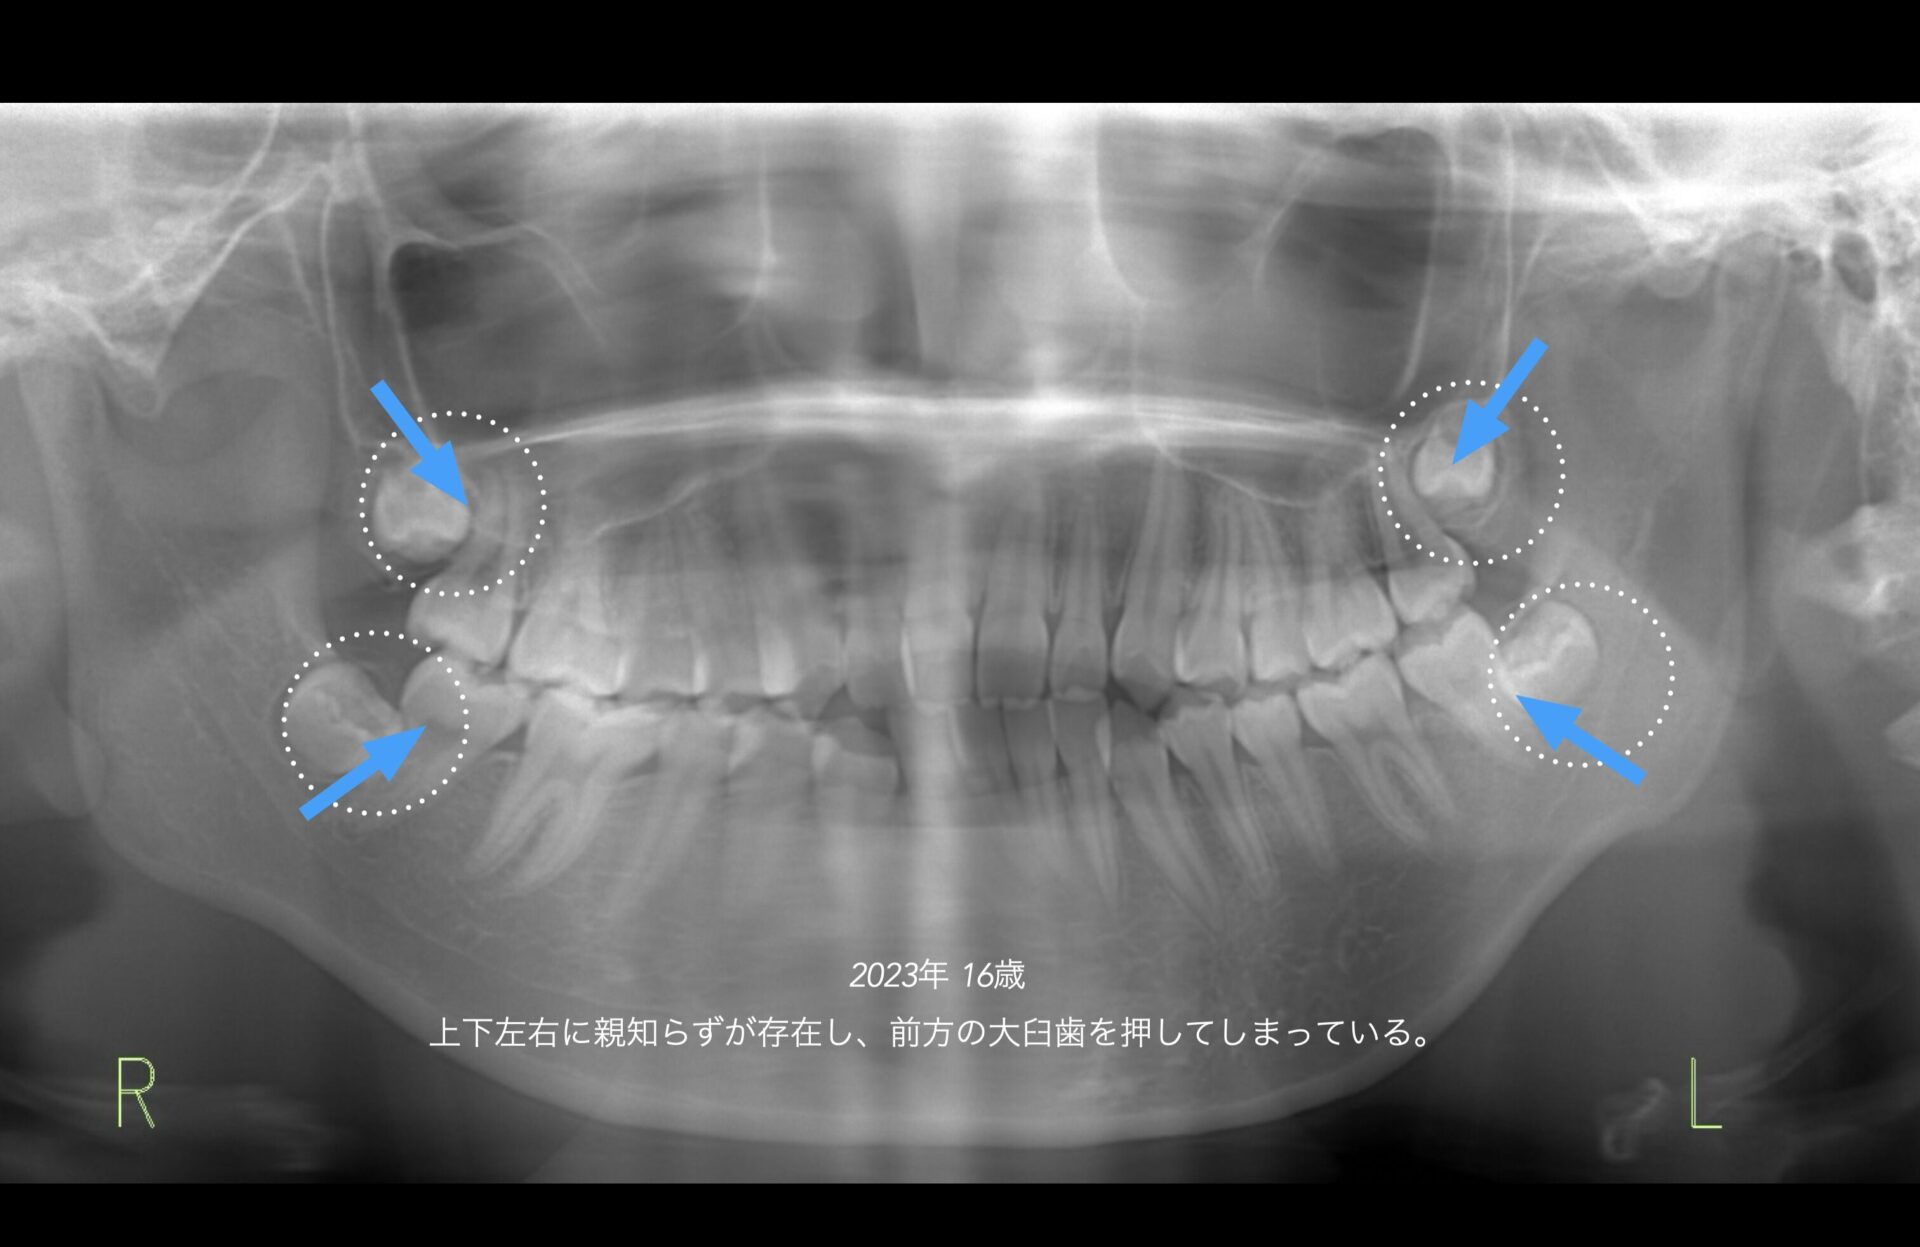

2023年 16歳 下方から見ると前歯は全くかめていない。

親知らずが上下左右存在する。下顎の前下方への成長を妨げている原因の一つと診断。下顎の親知らずを抜歯してから矯正をスタートする。